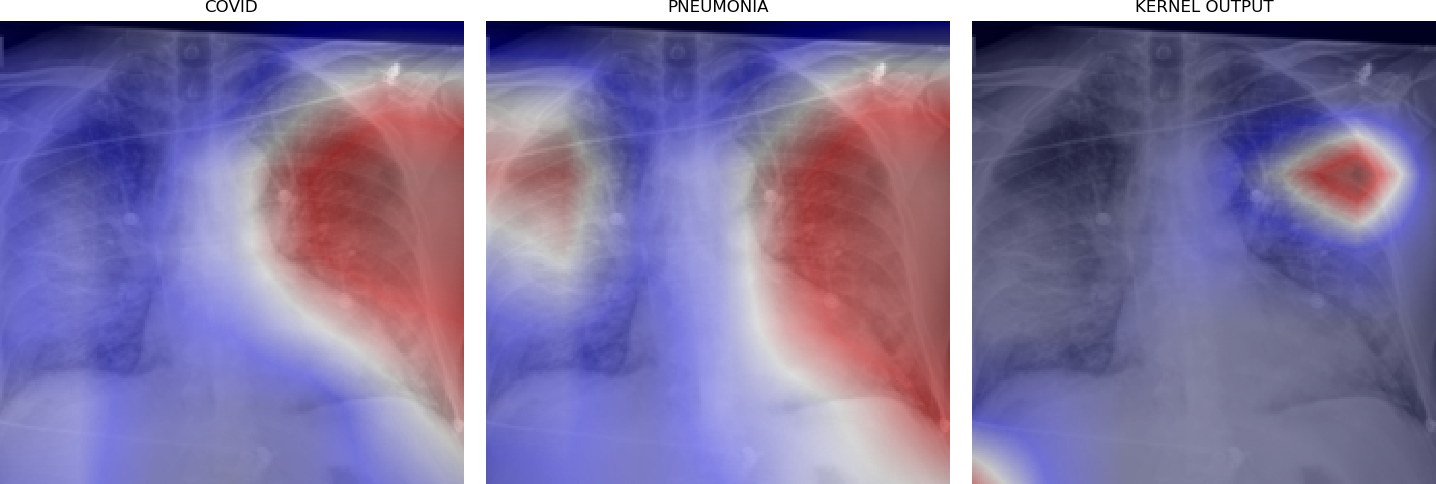

Figure 5 shows triples of X-ray images with superimposed class activation maps for predictions obtained from expert binary models (images one and two) with the third image showing the heat maps computed using our kernel. The intended use of our method is to examine positive classifications from two possibly overlapping classes (i.e. COVID-19, Pneumonia) and extract discriminative features pertaining to the class of interest, i.e. COVID-19. Triples (a)-(f) show positive classifications of COVID-19 and Pneumonia by their respective binary expert models along with class activation maps that localize the image region responsible for that classification. The third image in each triple shows a better localized image region for COVID-19 as computed using our method. Our method is intended to improve explainability of predictions under circumstances where both models return positive classifications resulting in significant overlap in activation maps.

Figure 6 demonstrates the role of the kernel parameter . It controls amplification of the directed differences among the activation maps. Higher values of concentrate the resulting heat map to a smaller region.